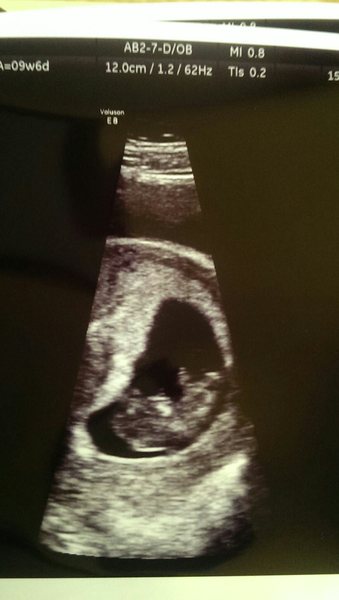

Scan this afternoon went well, there's definitely a baby in there, we heard the heart beat and the measurements were exactly the same as my dates. Feel very reassured and it was lovely to see DH beaming at the screen Smile 12 week scan is on 30th Dec.

9+6